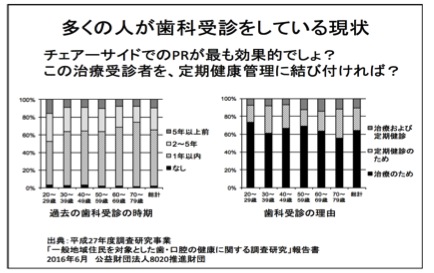

そうなんです。痛くないと歯医者さんに行かないのが日本人。こちらのデータをみて下さい

日本人はきちんと歯医者さんに通うんですが治療のために通う場所になってしまっています。治療って怖いし、症状がある時だと痛いし、トラウマが強いんです。なので、痛みが出るまで、我慢できなくなるまで通わない、ということになる。